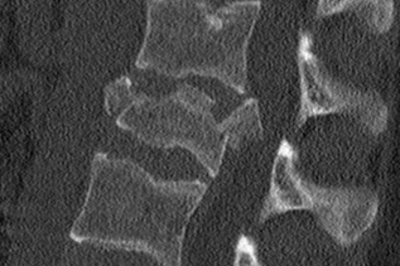

• Röntgenbild Wirbelfraktur

Röntgenbild Wirbelfraktur

Traumatische, craniale Berstungsfraktur mit Bandscheibenruptur